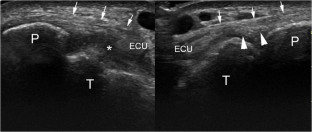

Fig. 4